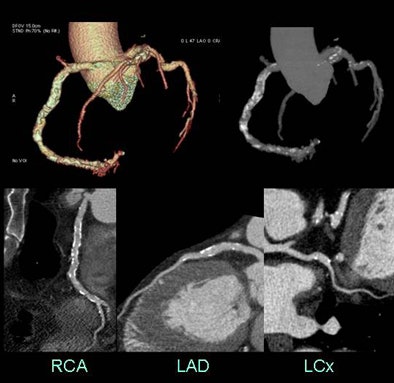

| High coronary calcium scores did not impede most diagnoses. Above, all 17 coronary artery segments were assessable at CTA in a 63-year-old man referred with abnormal myocardial perfusion, chest pain, and a calcium score of 3,215. Images were acquired at 650 mA, 120 kV, 50 msec padding, and an effective dose of 2.53 mSv. Conversely, three segments in the case below were not assessable in a 57-year-old man with a calcium score of 2,318 presenting with shortness of breath and chest pain. CTA was acquired at 750 mA, 120 kV, 75 msec padding, and an effective dose of 5.34 mSv. |